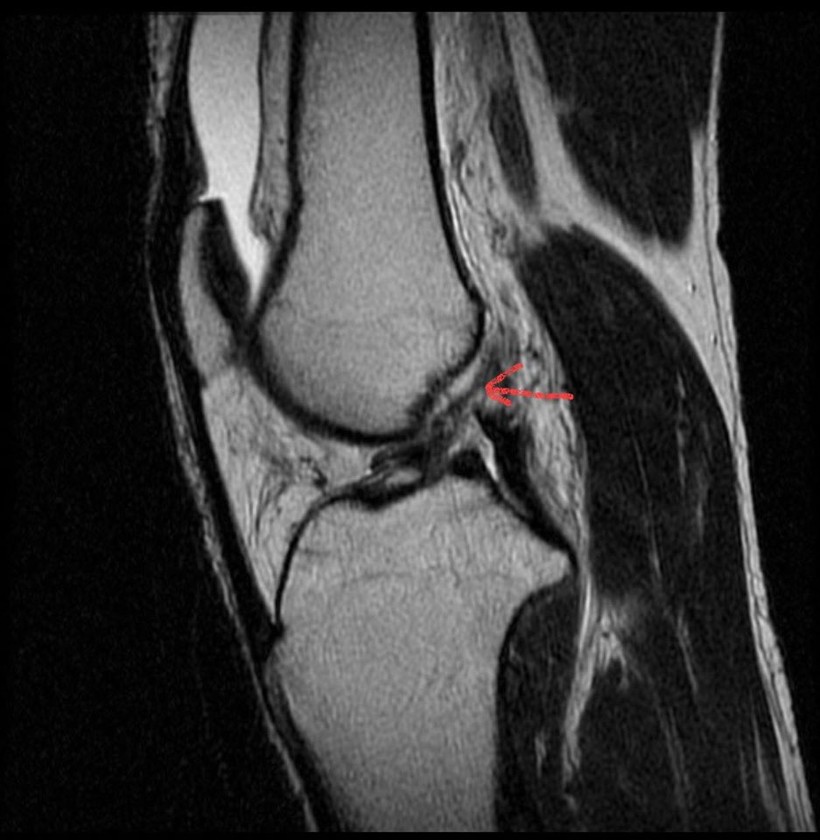

![]() |

| Dây chằng chéo trước ccủa bệnh nhân sau khi được tái tạo thành công. Ảnh: BVCC |